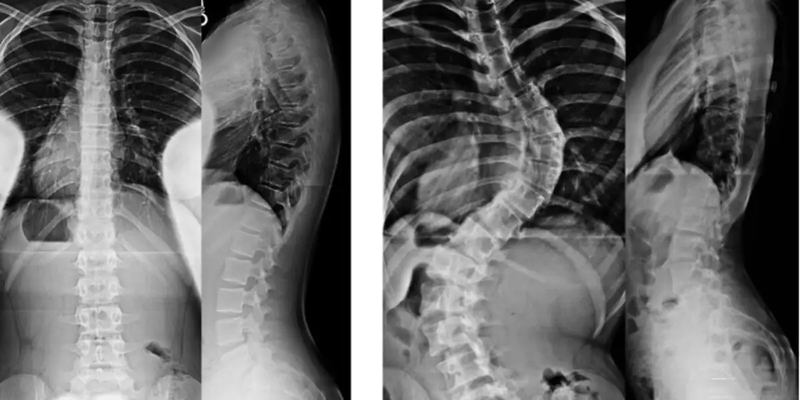

Để chẩn đoán chứng vẹo cột sống bẩm sinh, bác sĩ sẽ khám sức khỏe và khai thác bệnh sử đầy đủ cho bé. Bác sĩ cũng có thể yêu cầu chụp X-quang để xem xét kỹ hơn hình ảnh của phần cột sống bị ảnh hưởng trên phim.

Khi chứng vẹo cột sống bẩm sinh đủ nghiêm trọng để cần điều trị, trẻ thường cần phải phẫu thuật. Nẹp và các phương pháp điều trị không phẫu thuật khác thường không hiệu quả đối với chứng vẹo cột sống bẩm sinh. Điều trị phẫu thuật sẽ phụ thuộc vào độ tuổi và giai đoạn tăng trưởng của bé.

Các phương pháp phẫu thuật cho trẻ mới biết đi và trẻ bị cong vẹo cột sống bẩm sinh: